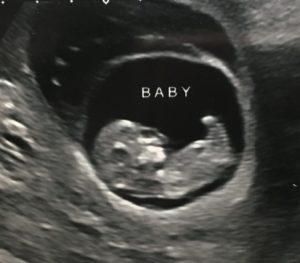

Baby at 11.1 weeks – the large bubble above baby is the subchorionic hematoma

I had fortnightly ultrasounds after this was discovered, to check it was going away. Over the next three ultrasounds, the hematoma continued to grow, and I was getting frequent bleeding and abdominal cramps, so with the support of my doctors I made the decision to stop work completely and I rested at home. The cramps soon went away with more rest, but I had bleeding almost every day for two months before it finally started to stabilize, and eventually the bleeding stopped.

By then, it was time for my anatomic ultrasound. I was feeling optimistic: I hadn’t had any bleeding for two entire weeks, and was beginning to feel some movement which gave me a lot of reassurance that baby was developing well despite all the drama.